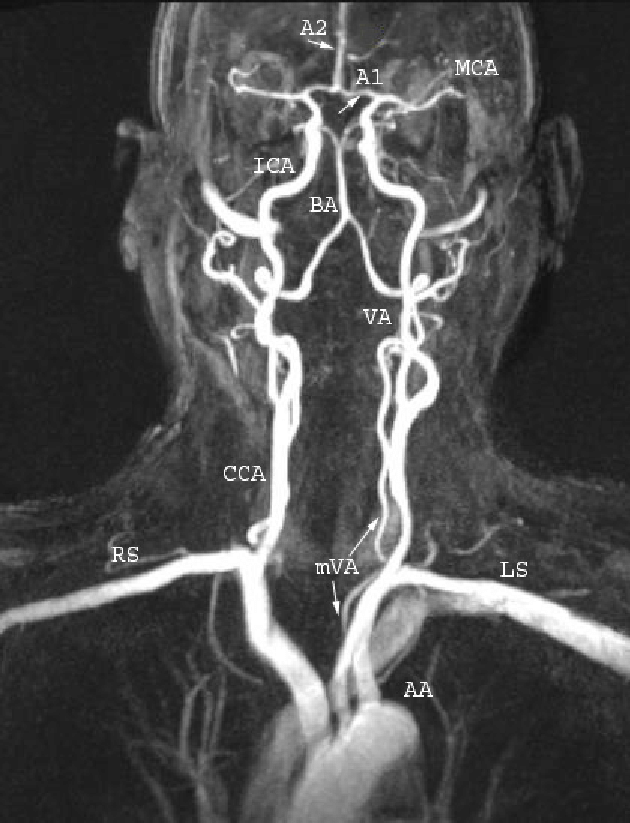

颈动脉和椎动脉是血流从心脏通往脑部的“高速公路”,这条高速公路不允许有“收费站”,更不允许道路上有障碍,车道必须保持完全通畅,才能保证脑部的血供,让我们脑部的神经中枢才能正常工作。“高速公路”一共有4条,左右各有两条较粗的颈动脉和两条较细的椎动脉,颈动脉主要供应大脑前部的血液,椎动脉主要供应大脑后部以及小脑和脑干的血液。所以这4条血管非常重要。闭塞就有可能造成脑梗死。